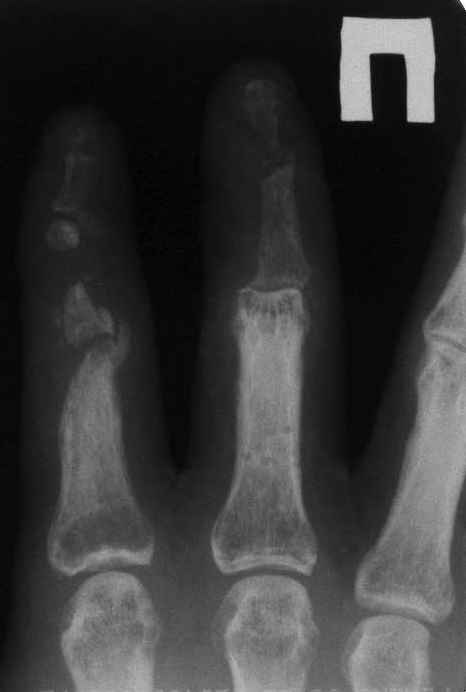

33 yo male motocross rider crashed after a jump sustaining isolated bilateral femur fxs, R side with a basicervical femoral neck and ipsilateral mid-distal 1/3 shaft, L side with a subtroch/prox 1/3 femur fx. Pt was HD stable, no LOC, GCS - 15, No other injuries, spines cleared.

Left side- same table/postion, antegrade nail

The left shaft fracture should accommodate an antegrade reamed locked nail after reduction, unless I¹ve missed some detail on the films as shown.

i would use an antegrade nail on the left